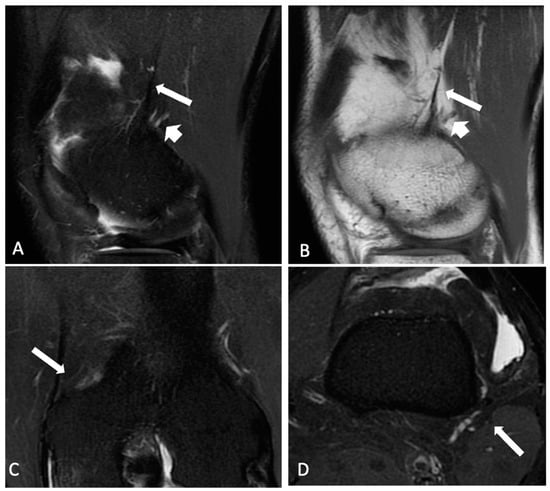

2.2. Radiological Analysis